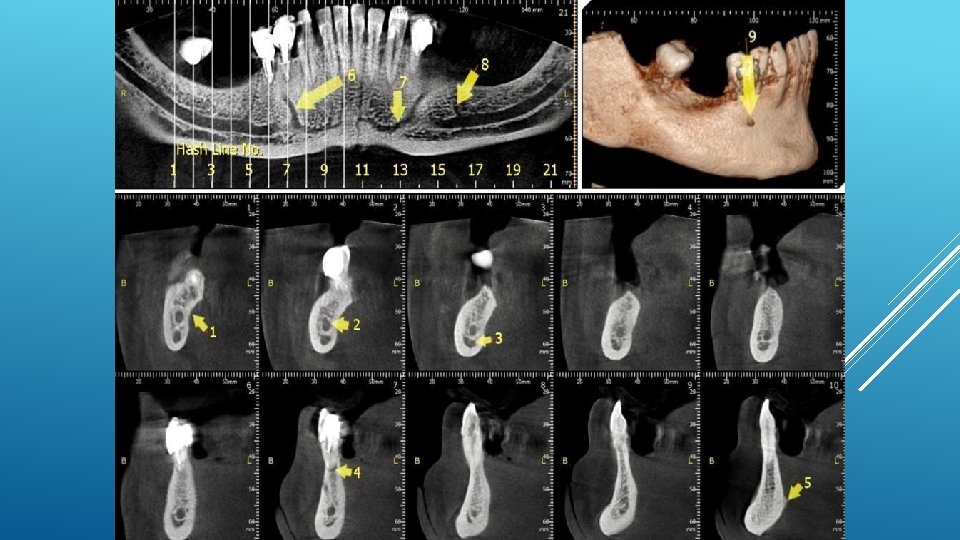

LOCATION AND DIMENSIONS OF THE MENTAL FORAMEN: A RADIOGRAPHIC ANALYSIS BY USING CONE-BEAM COMPUTED TOMOGRAPHY The majority of MF (56%) were located apically between the 2 premolars, and another 35. 7% of MF were positioned below the second premolar. On average, the MF was localized 5. 0 mm from the closest root of the adjacent tooth (range, 0. 3 -9. 8 mm). The mean size of the MF showed a height of 3. 0 mm and a length of 3. 2 mm; however, individual cases showed large differences in height (1. 8 -5. 1 mm) and in length (1. 8 -5. 5 mm). All mental canals exiting the MF demonstrated an upward course in the coronal plane, with 70. 1% of the mental canal presenting an anterior loop (AL) in the axial view. The mean extension of AL in cases with an AL was 2. 3 mm.